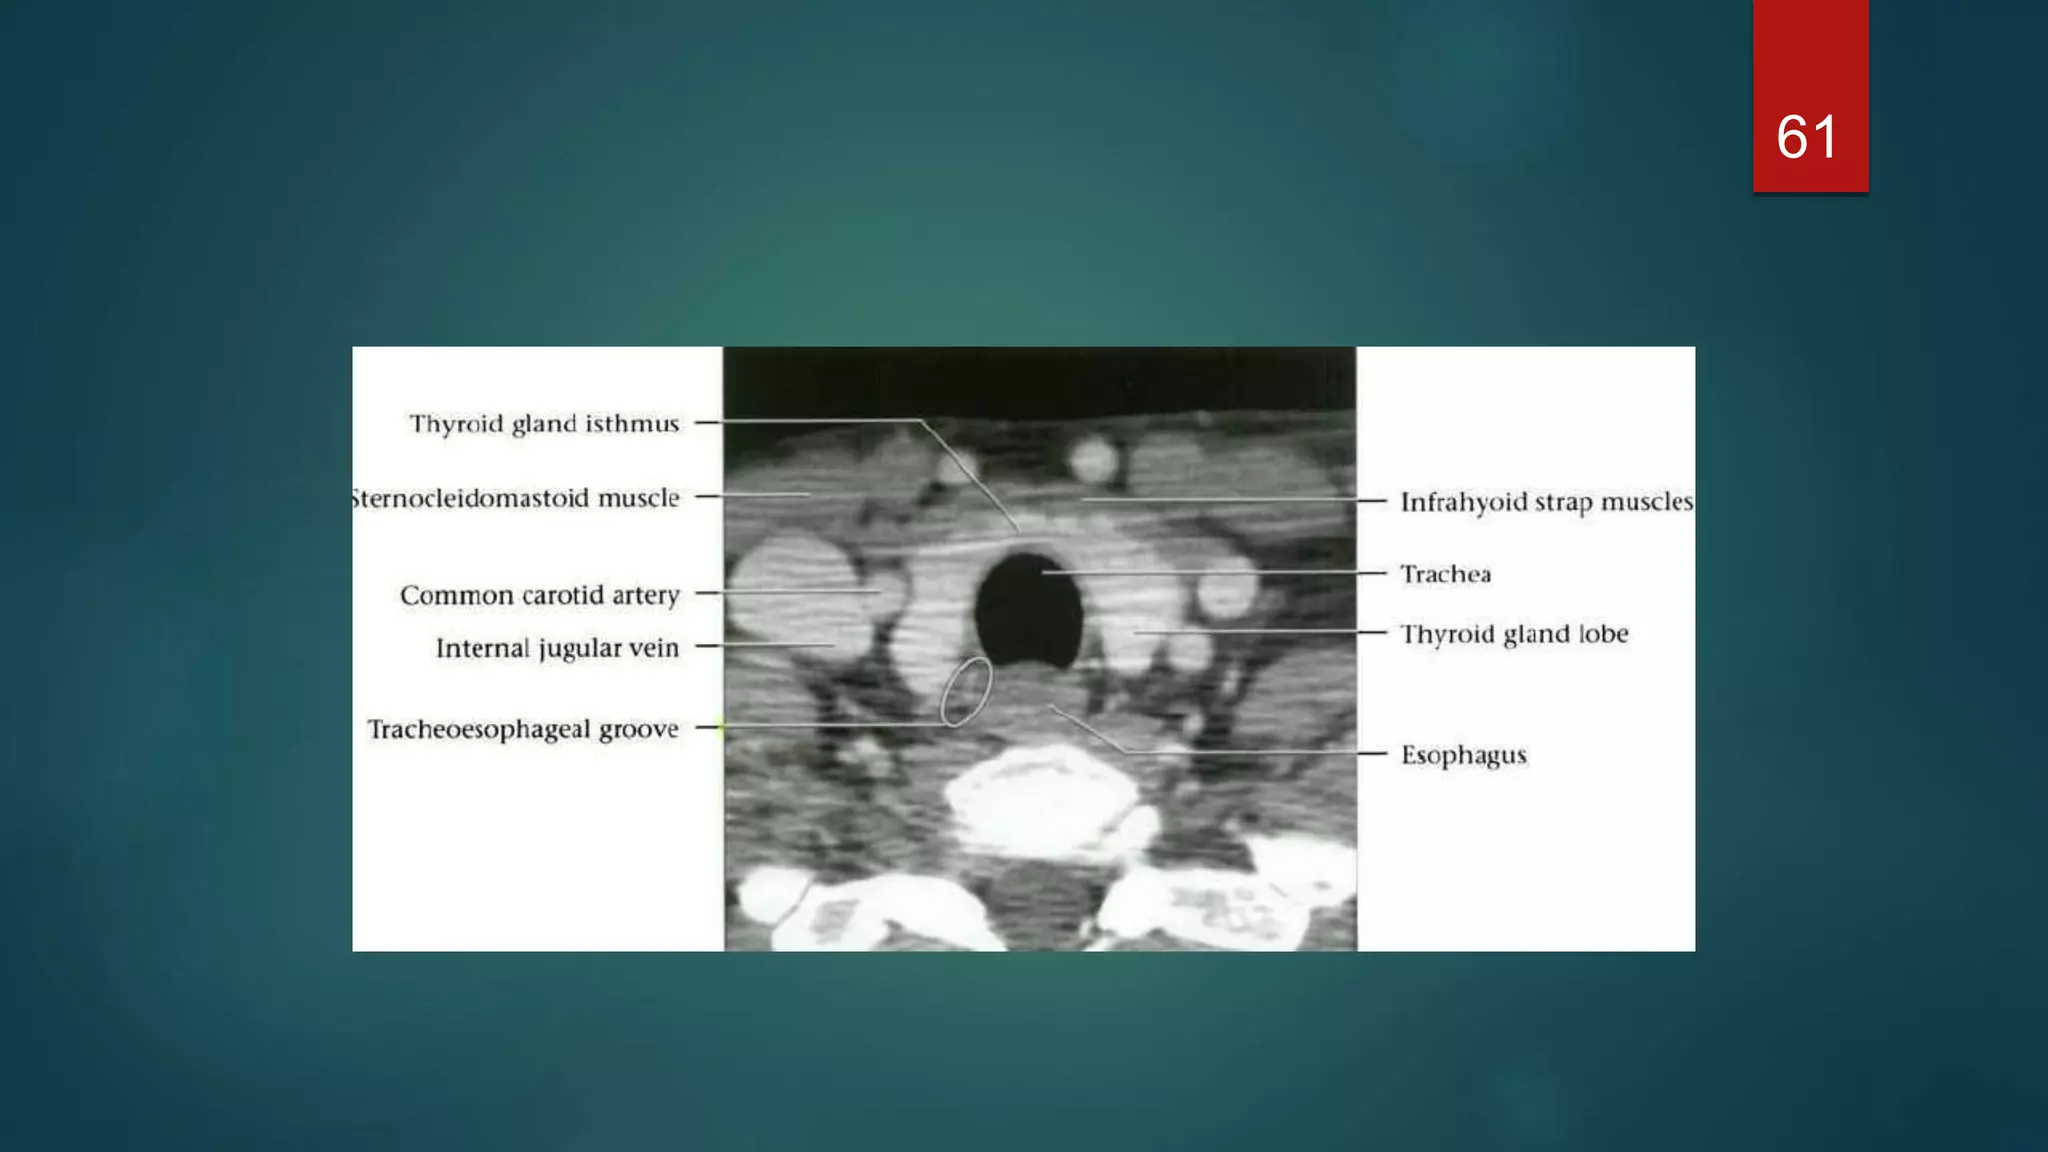

 The thyroid gland consists of two lateral lobes joined by a midline isthmus, and

lies anterior and lateral to the trachea.

 The lobes extend from the thyroid cartilage superiorly to the sixth tracheal ring

inferiorly

 Posterolaterally are the neck vessels, Behind these, on either side, are the

prevertebral muscles

 Anterior to the gland are the strap muscles of the neck and the sternomastoid

muscles

 The thyroidgland consists of two lateral lobes joined by a midline isthmus, and lies anterior and lateral to the trachea.  The lobes extend from the thyroid cartilage superiorly to the sixth tracheal ring inferiorly  Posterolaterally are the neck vessels, Behind these, on either side, are the prevertebral muscles  Anterior to the gland are the strap muscles of the neck and the sternomastoid muscles 57